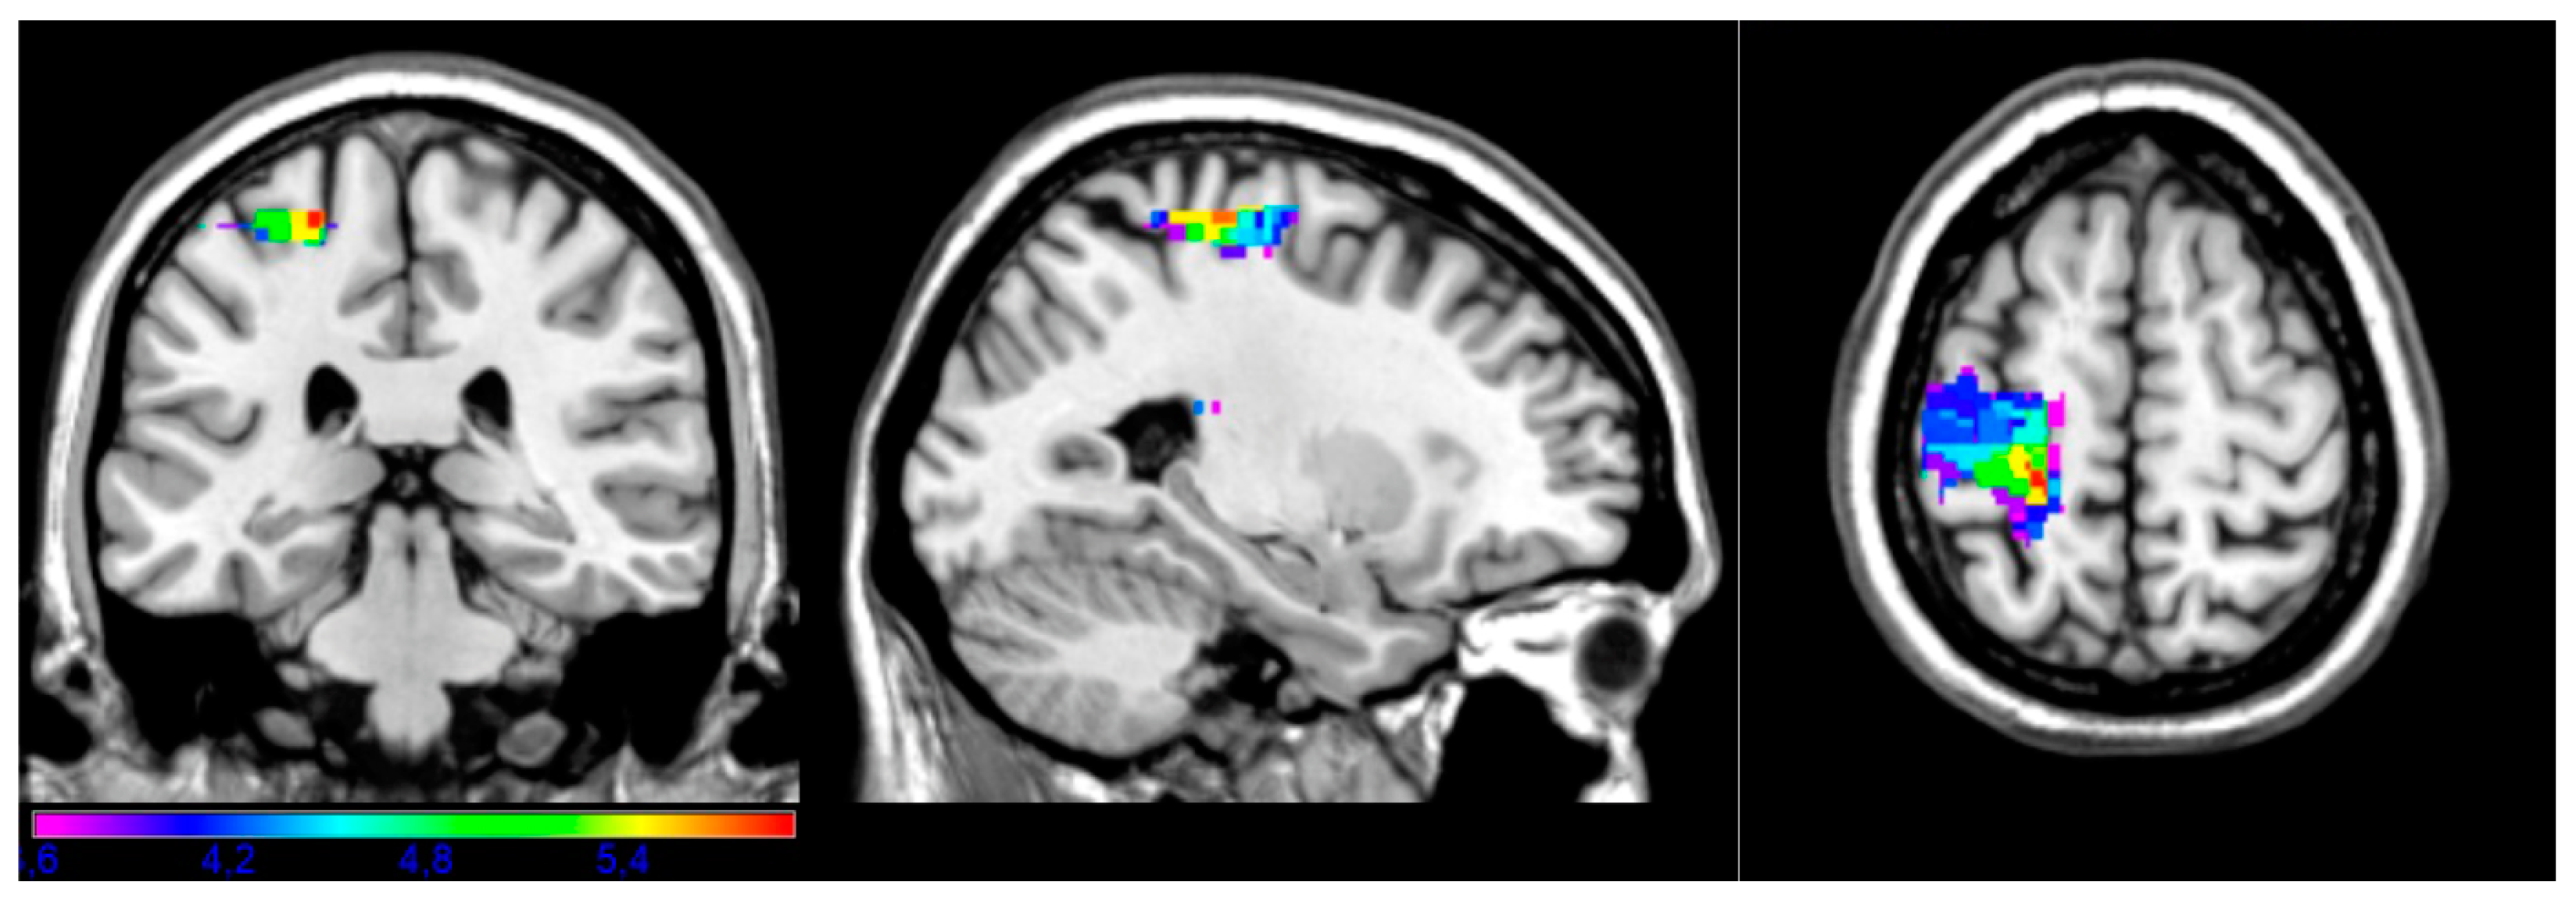

| Subtest | Volume | Px | Py | Pz | Min T | Max T |

|---|---|---|---|---|---|---|

| Complex | 614 | −24 | −30 | 62 | 3.60 | 5.89 |

| Instrumental | 356 | −14 | −44 | 58 | 3.61 | 5.99 |